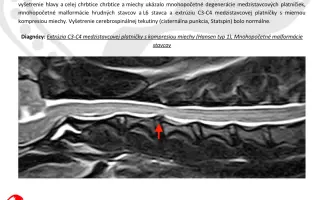

Pomoc smeruje môjmu 2-ročnému psíkovi Teovi, ktorý aj napriek mladému veku bojuje s vážnym ochorením chrbtice. Veterinárne vyšetrenia ukázali:

- extrúziu C3–C4 medzistavcovej platničky,

- kompresiu miechy,

- mnohopočetné malformácie stavcov.

Ide o vážny stav, ktorý spôsobuje silnú bolesť, slabosť končatín a môže veľmi rýchlo viesť až k úplnému ochrnutiu. Veterinári nám jednoznačne potvrdili, že operácia je nevyhnutná, inak Teovi hrozí trvalé postihnutie.